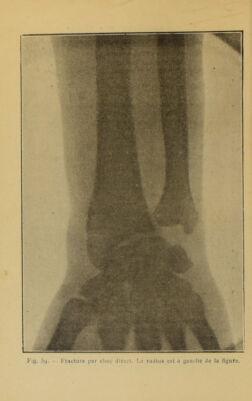

Hygiène du chauffeur : le moteur humain / par R. Bommier ; préface du Comte Mortimer-Mégret.

Credit: Hygiène du chauffeur : le moteur humain / par R. Bommier ; préface du Comte Mortimer-Mégret. Source: Wellcome Collection.